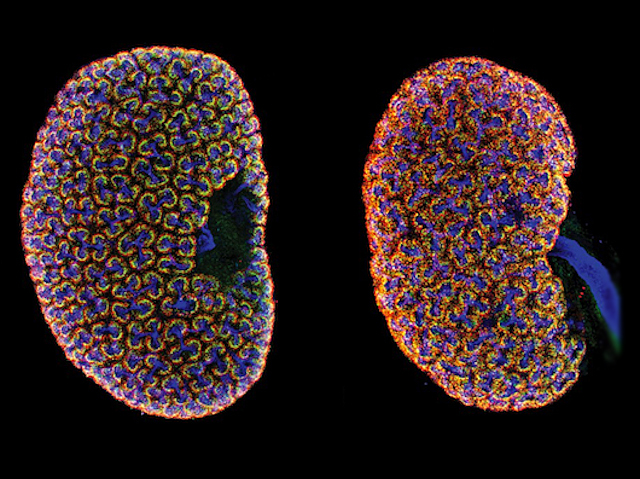

You’ve got around 2 million of them – nephrons, tiny filters in your kidneys that clear out the waste products in your blood. The right numbers of nephrons are produced during development by cells called nephron progenitors. A pool of these progenitors is maintained, with a steady stream maturing into different nephron cells. This fine balance is sustained by signalling molecules called Wnts. Researchers dig deeper by focusing on Wnt11, which accumulates at the tips of developing kidney branches where nephron progenitors live. Fluorescent imaging of kidneys from mutant mice lacking Wnt11 (pictured, right) revealed that the progenitors lost their sense of orientation, revealed by the polarised distribution of the protein desmin (green) within these cells being disrupted compared to normal kidneys (left). Mutants also depleted their pool of progenitors faster, resulting in half the number of nephrons and smaller kidneys. Wnt11 is therefore a major player in kidney development.